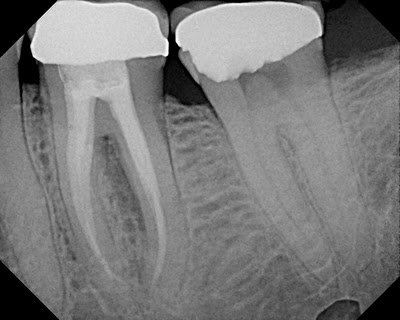

The tooth is deemed non-restorable and extraction recommended.

If you are unsure if a tooth has a cracked/fractured root, contact your endodontist. Not all teeth can be saved, but endodontists are the specialists for saving teeth and can help you determine which ones to save.